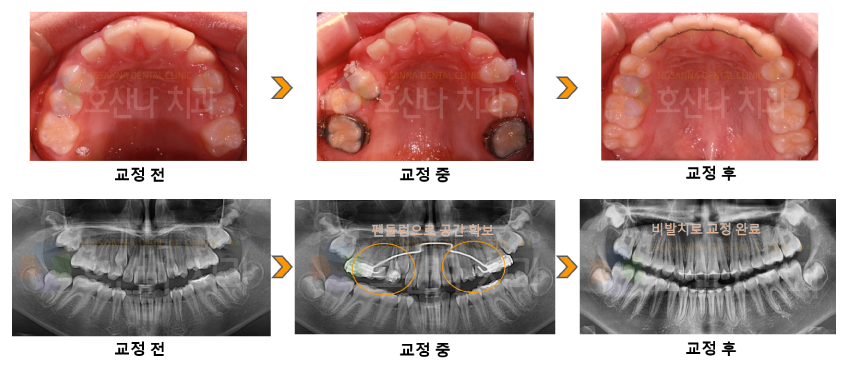

교정비발치 펜듈럼 교정 시술 증례

< 비발치 펜듈럼교정 시술 증례 >

1. 치료대상

female / 10y 6m

2. 교정치료이유

영구치가 나올 자리가 부족한 것 같아요

3. 진단결과

1) Skeletal CL I

2) U crowding / II canine and molar relation

3) Deep bite

4. Dr.Koo Memo

상,하악의 영구치를 위한 공간이 상당히 부족하였습니다.

약간의 돌출감은 있었지만 환자 본인과 보호자는 돌출 개선을 원하지 않으셔서 최대한 발치 없이 펜듈럼 교정을 시행하였습니다.

펜듈럼 기간은 8개월 시행하여 구치부를 최대한 후방 시키고  교정 완료 하였습니다.

통증이 없고 브라켓 붙히는 기간도 짧아 아이들에게는 오히려 유리한 교정입니다.

5.교정기간

2y